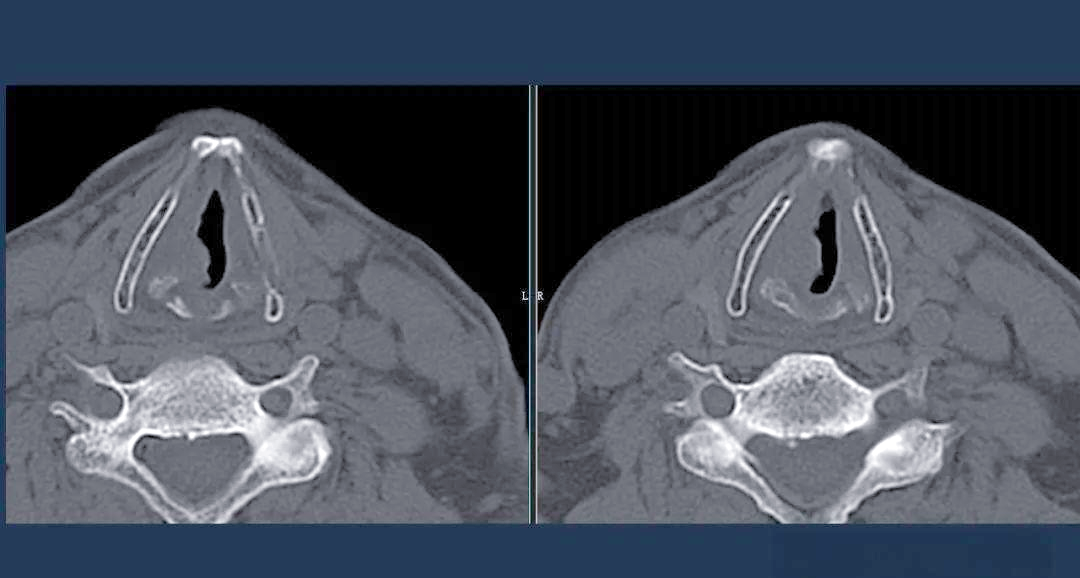

喉癌的ct,mri诊断

图片尺寸960x720